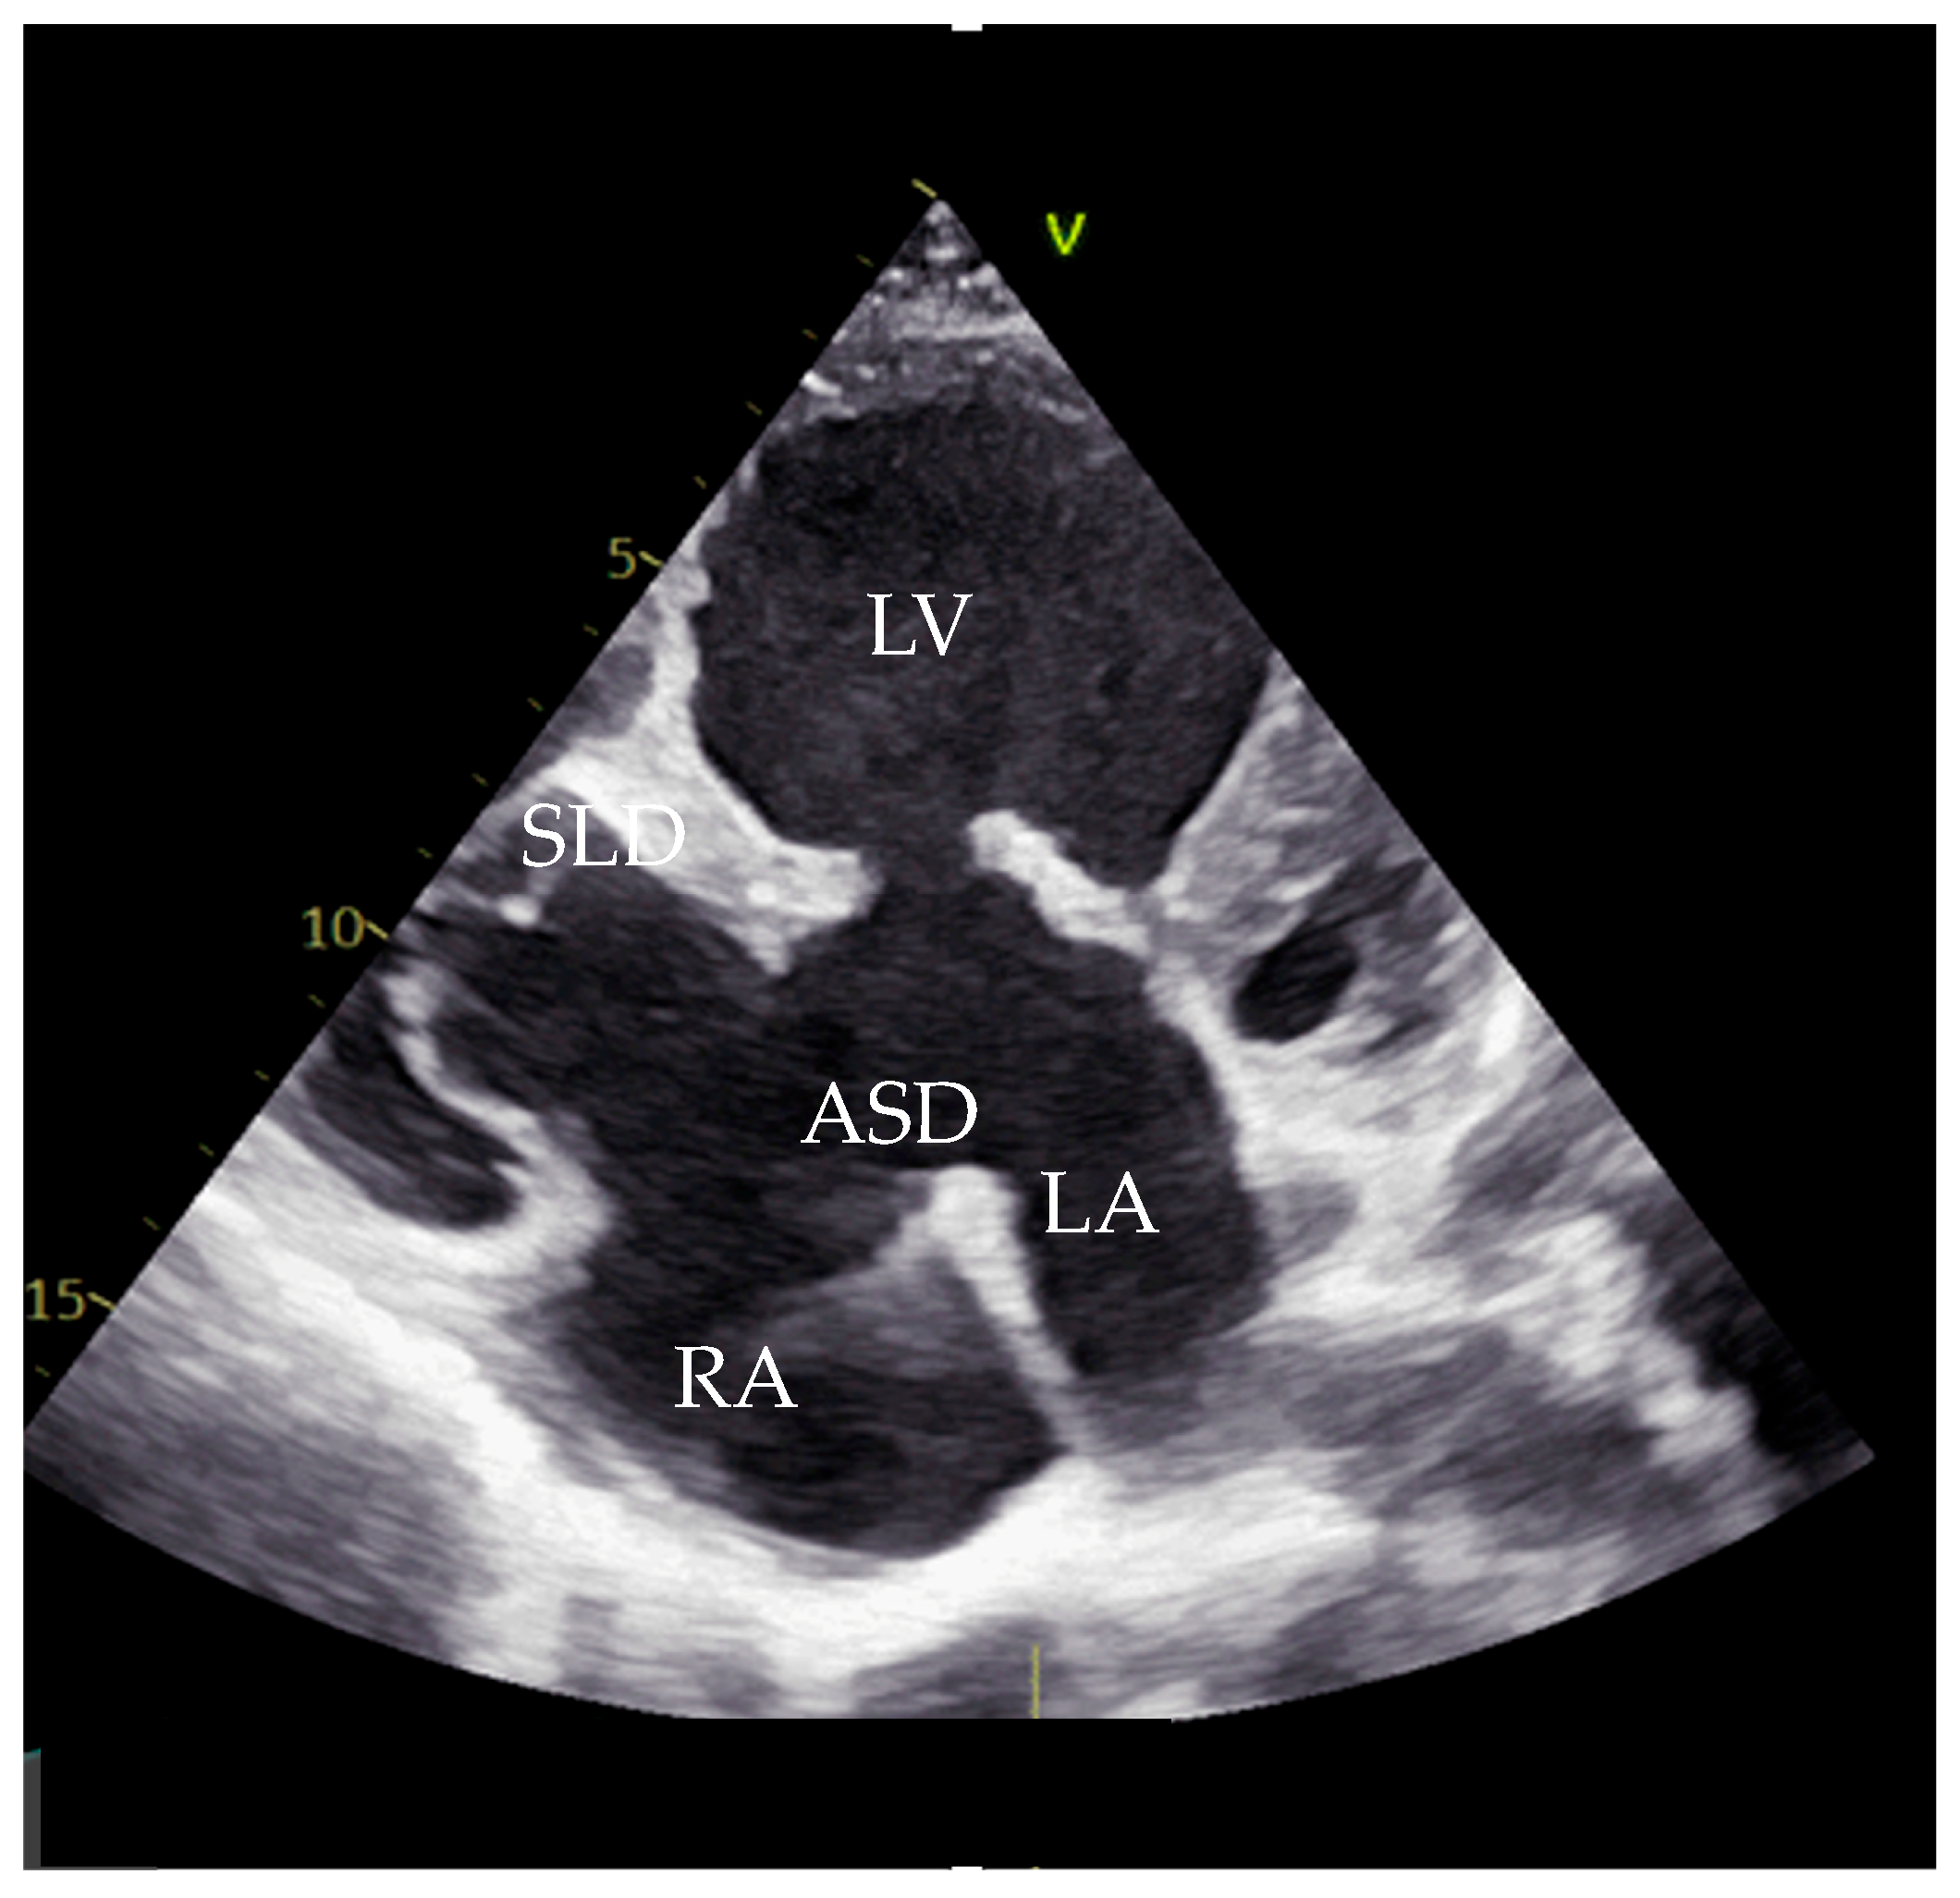

Cardiac catheterization revealed normal pulmonary artery pressures (19/10/15 mmHg), a pulmonary vascular resistance (PVR) of 1.5 Wood units/m2, and a Qp/Qs ratio of 2.3 (Figure 3).

Figure 3. Angiography finding focusing on RV and RVOT. RV—right ventricle, RVOT—right ventricular outflow tract, PA—pulmonary artery.